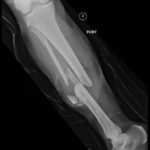

Plain film shows severely comminuted and displaced mid tibia/fibula fractures of bilateral lower extremities (red arrows) and comminuted right fibular head (blue arrow) and proximal shaft fracture (yellow arrow).

The patient in this case was given intravenous cefazolin and was taken to the operating room the same day by orthopedic surgery for bilateral lower extremity tibia and fibula open reduction and internal fixation.